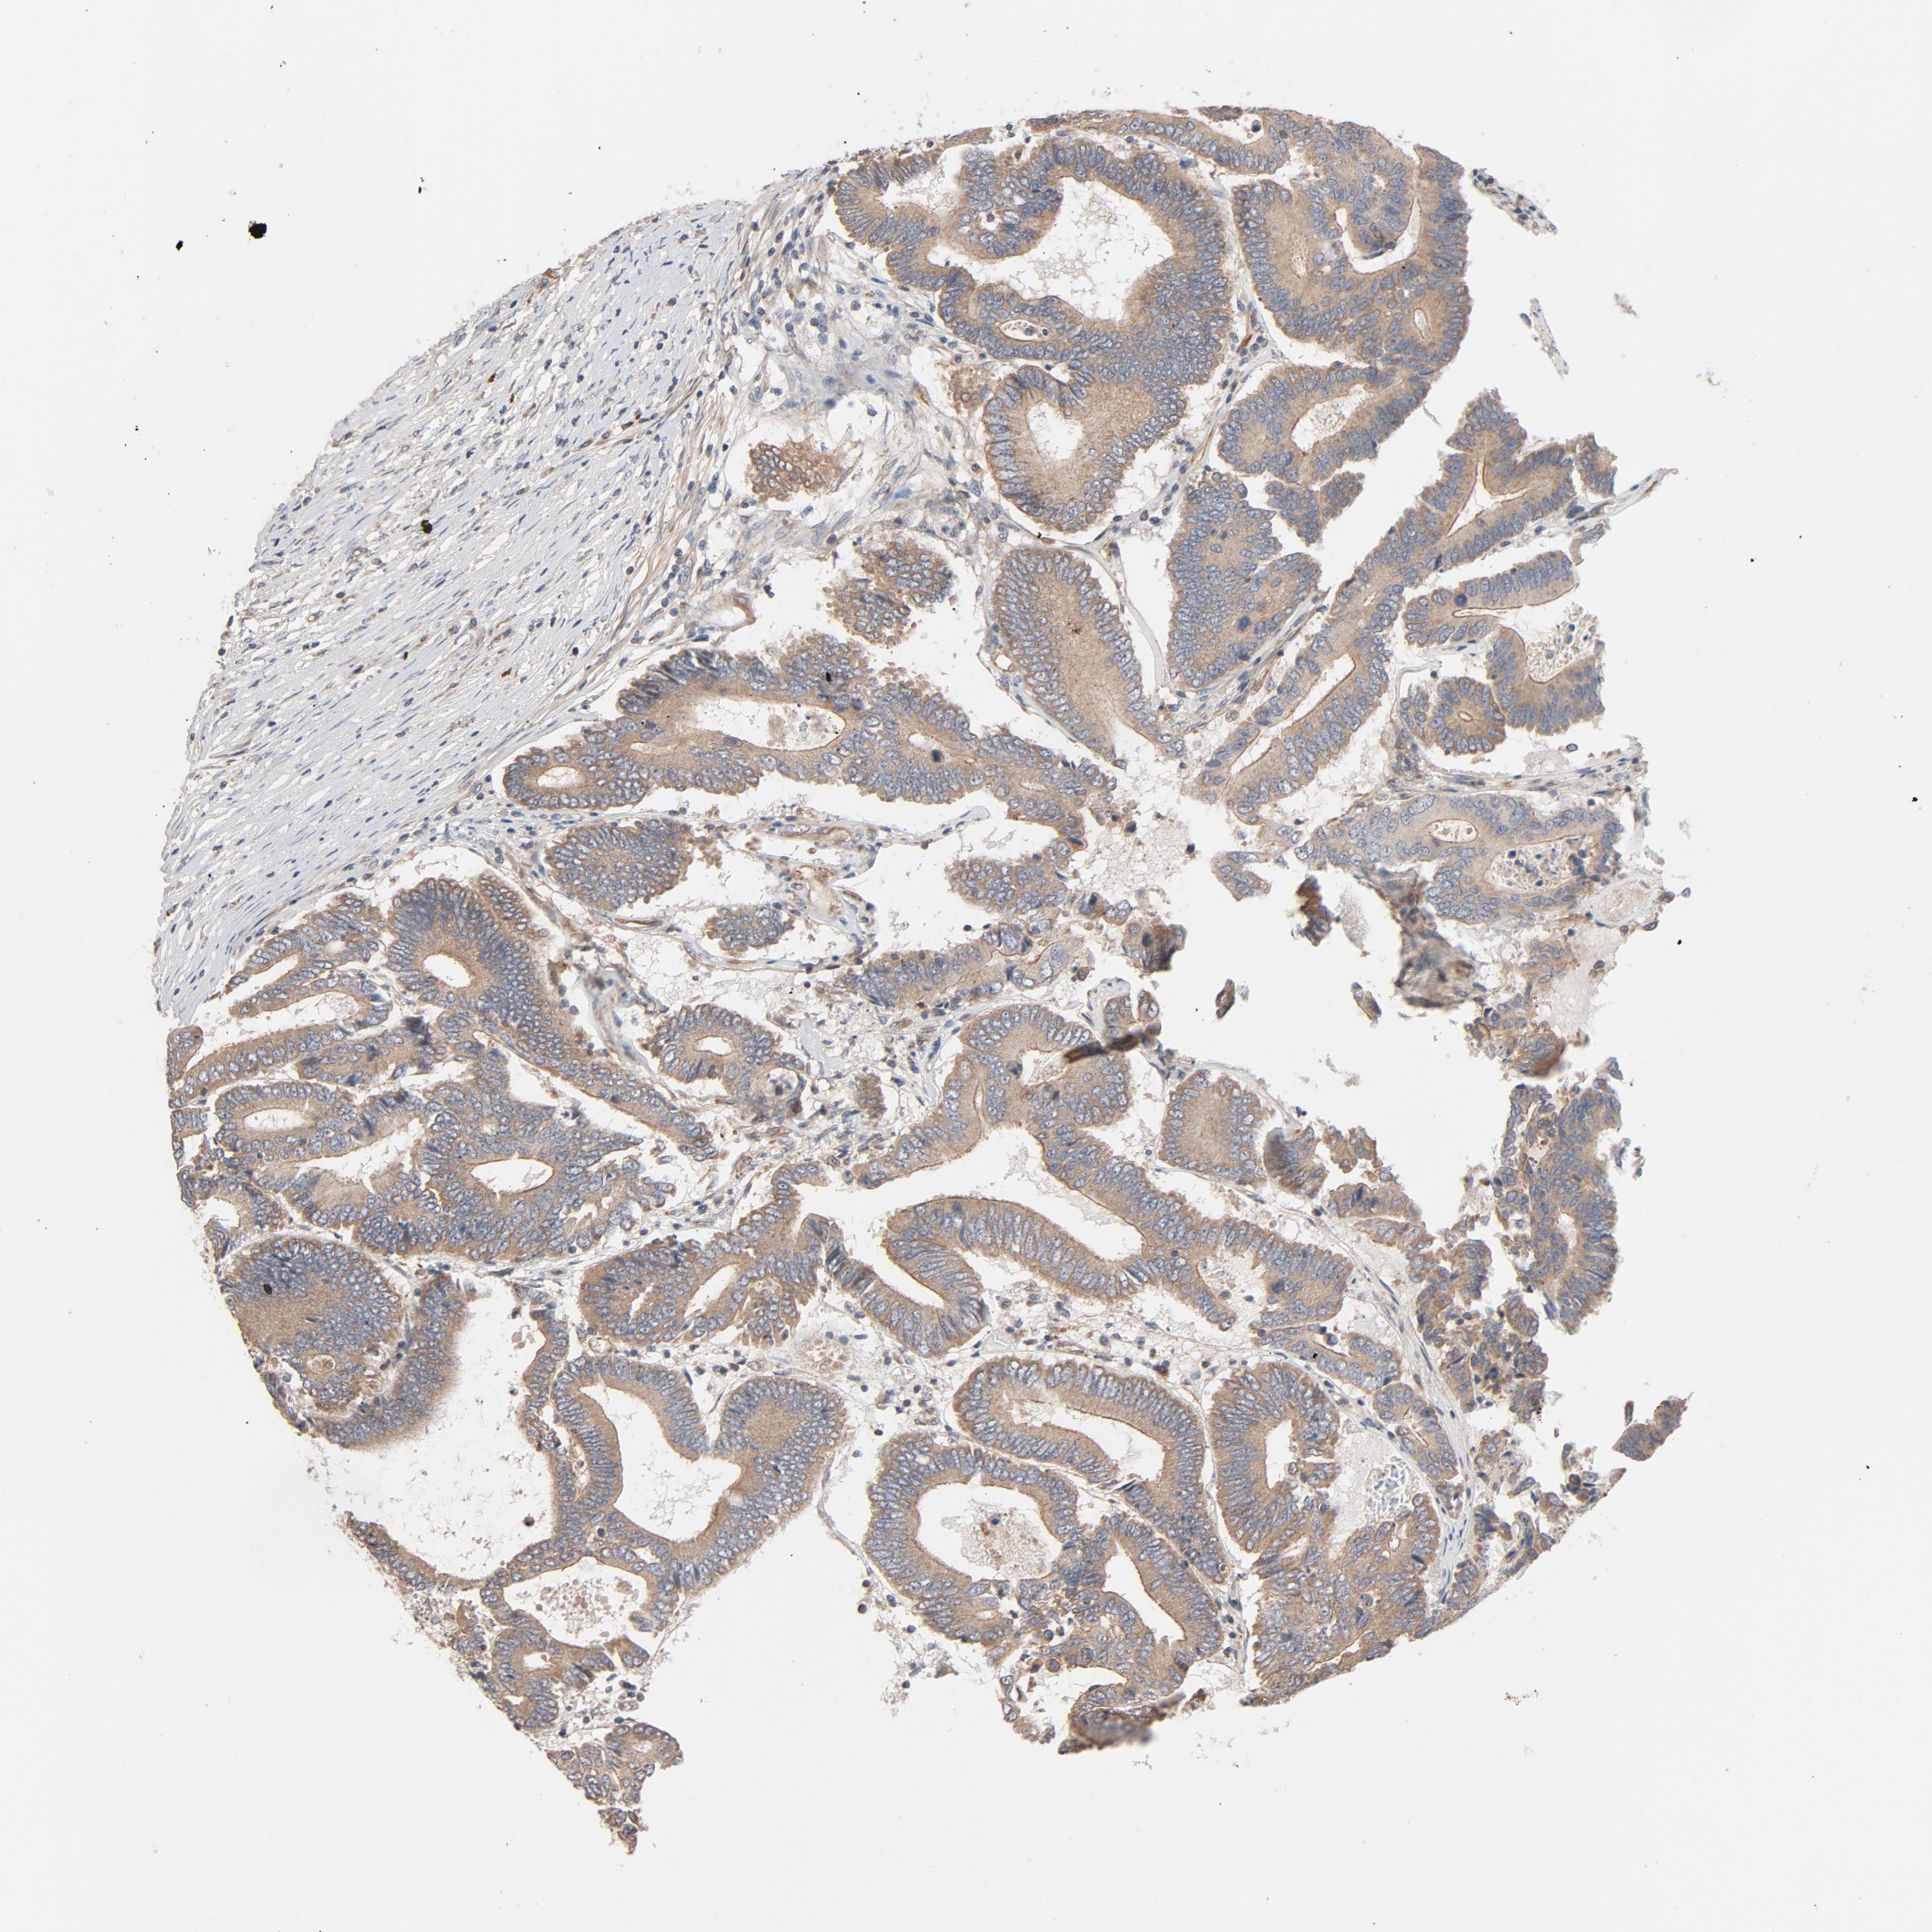

CANCER COLORECTAL CANCER Show tissue menu

Colorectal cancer

Human cancer

Colon adenocarcinoma

Rectum adenocarcinoma